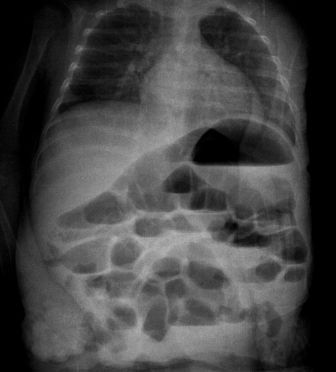

На рентгенограмме - множественные горизонтальные уровни в просвете кишки, контрастирования газа в проекции печени нет(к слову - иллюстрация того, что горизонтальные уровни в кишечнике не обязательно признак кишечной непроходимости, стул у ребёнка кашицеобразный за последние 12 часов - 4 раза)